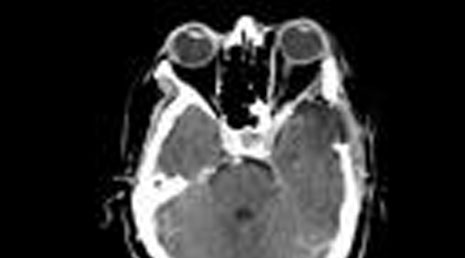

20. cholestatoma